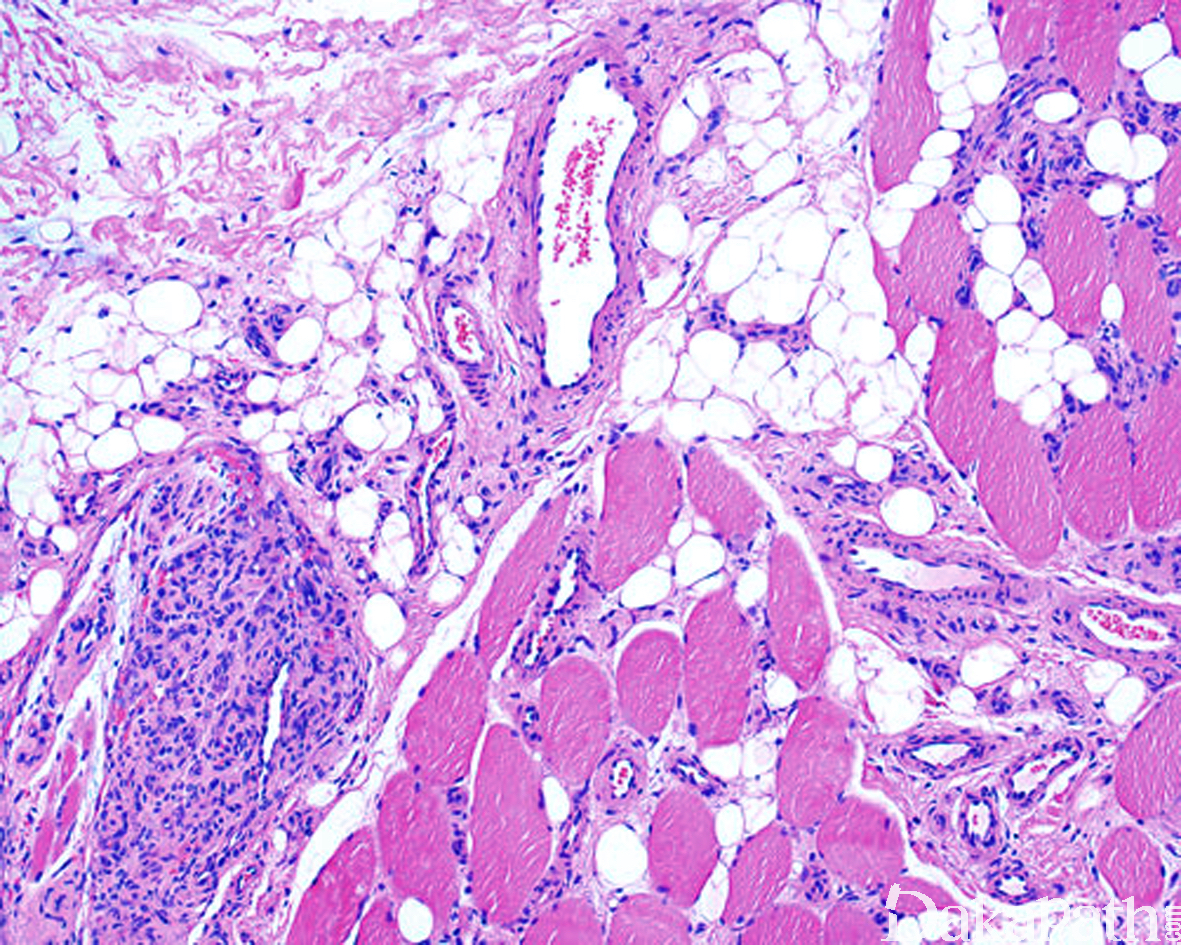

镜下:肌内血管增生,常界限不清, 周围骨骼肌组织常伴有成熟脂肪化生;

血管瘤形态多样,常由厚壁静脉、动脉、毛细血管、扩张的厚壁血管混合组成,也可伴有淋巴管;

可表现为毛细血管型、海绵状血管型或混合型。